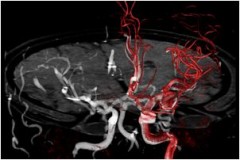

コーンビームCTテクノロジーの最新アプリケーションであるVasoCT*1による3Dイメージングも、「NeuroSuite」を構成する重要なアイテムである。16bitのFPDによる頭蓋内の穿通枝レベルの微細な血管や周辺解剖および最新デバイスの描出*4は、脳血管内治療のイメージガイダンスとして強力なサポートツールとなる。

脳血管内治療におけるイメージガイダンスで 必要とされる情報を効率よく術者に提供するために、「NeuroSuite」では様々なアイテムをライナップしている。改良された新型頭部固定具*1、MR/CT画像とのオーバーレイによる3Dロードマッピング機能*1、脳血流の潅流状態を評価する2D Perfusion*1、そしてこれらを術中にモニタリングする大型マルチレイアウトモニタ FlexVisionXL*1により脳血管内治療をより安全により確実にサポートする。